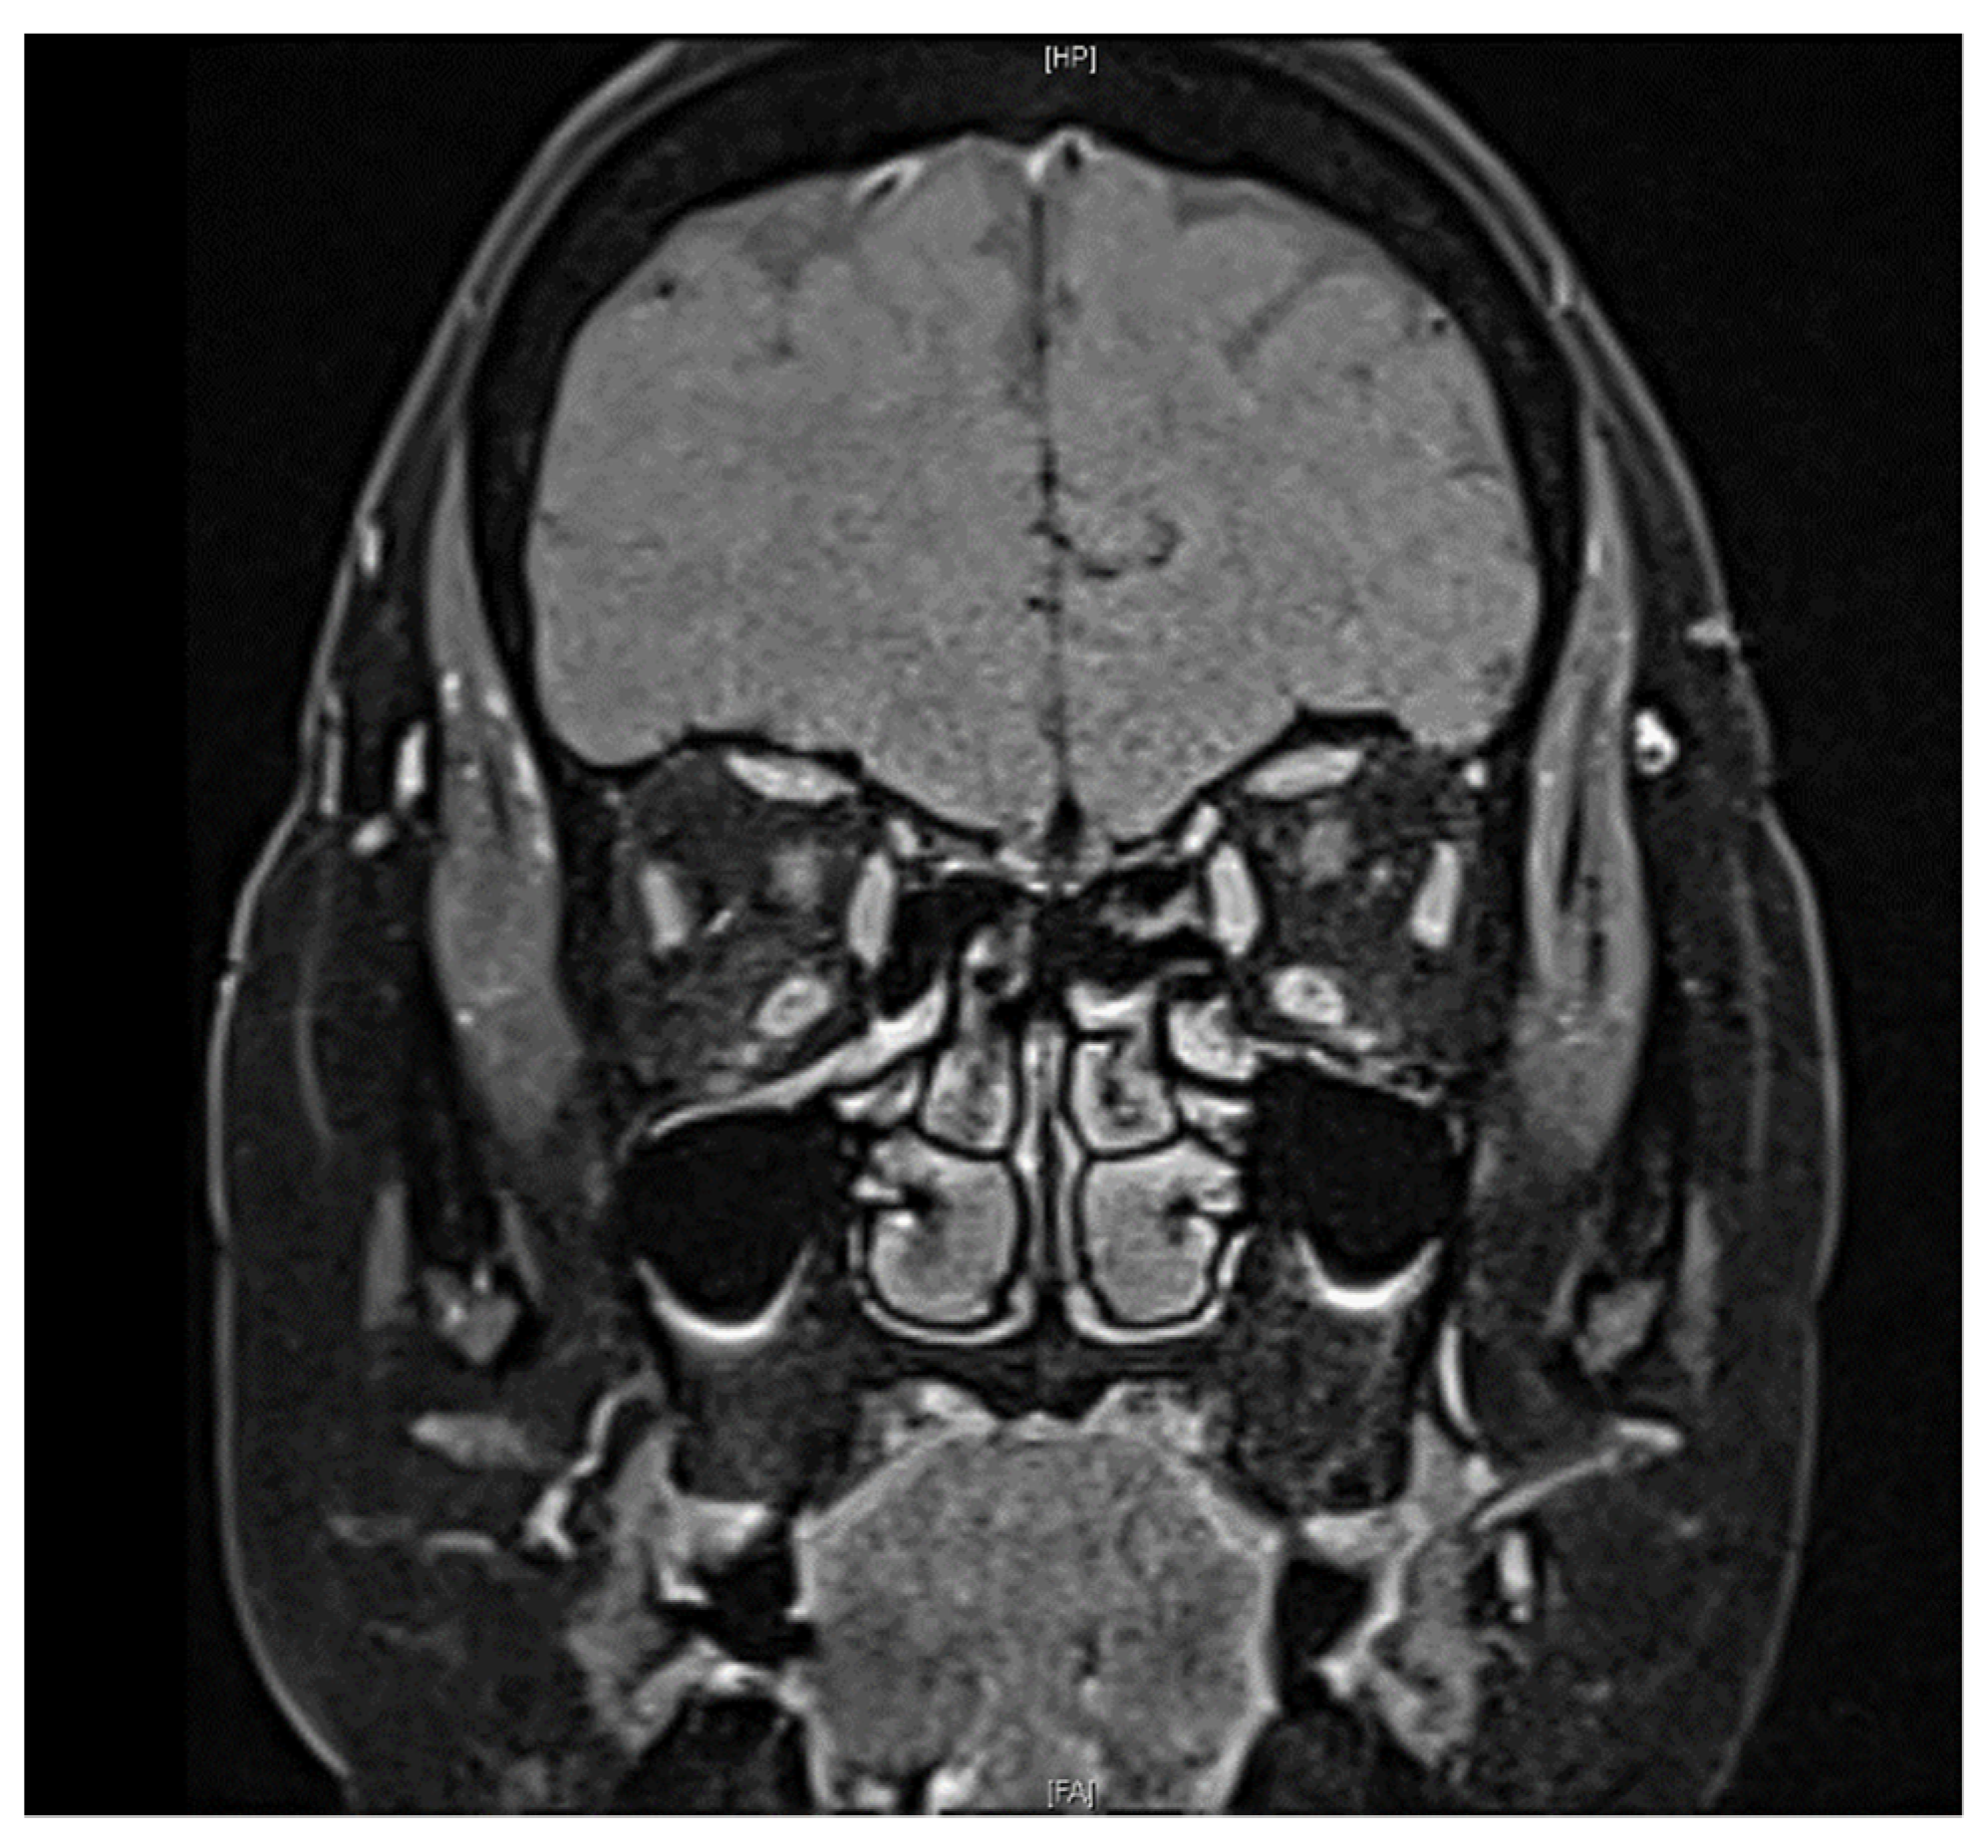

A 61-year-old female with a past medical history of controlled hypertension and borderline hyperlipidemia experienced sudden painless blurred vision in the left eye upon awakening. This patient had received the first dose of the ChAdOx1 nCoV-19 (AstraZeneca) vaccine seven days before the onset of her ocular symptoms. She suffered from an initial black shadow in the inferior quadrant with hazy vision upon awakening and had a headache in the temporal region. No other systemic symptoms regarding giant cell arteritis, such as scalp tenderness and jaw claudication, were noticed. She had a history of cataract surgery in both eyes (left eye: a year ago; right eye: seven months ago) without acute vision loss. On ophthalmic examination, her visual acuity was 20/20 and 20/50 in the right and left eye, respectively. No relative afferent papillary defect (RAPD) or color blindness were noted in either eye. Her intraocular pressure was within a normal range (right eye: 12.7 mmHg; left eye: 17.6 mmHg). Fundoscopic examination revealed a normal cup-to-disc ratio in both eyes (0.3/0.3) and pinkish optic disc with clear margin in the right eye, but optic disc edema (Frisen scale grade 2) in the left eye (Figure 1a). Humphrey 30-2 visual field testing identified an inferior altitudinal visual defect in the left eye. Optical coherence tomography (OCT) showed peripapillary retinal nerve fiber layer (pRNFL) edema and thinning of the macular ganglion cell layer (GCL) in the superior hemisphere in the patient’s left eye, corresponding to an inferior altitudinal visual defect (Figure 2). Fluorescein angiography revealed filling delay, decreased choroidal perfusion, and optic disc leakage. Neither obvious edema nor increased contrast medium enhancement of bilateral optic nerves was shown on the MRI of brain (Figure 3), and therefore, the patient was less likely to be a case of optic neuritis. To exclude giant cell arteritis, laboratory studies were examined, including full blood count, erythrocyte sedimentation rate (ESR), and D-dimer, showing normal results. In addition, the antinuclear antibody (ANA) and rapid plasma reagin (RPR) tests were both negative.

Figure 3. Fat-suppressed T1 coronal image on MRI revealed no contrast enhancement of the optic nerve in both eyes.